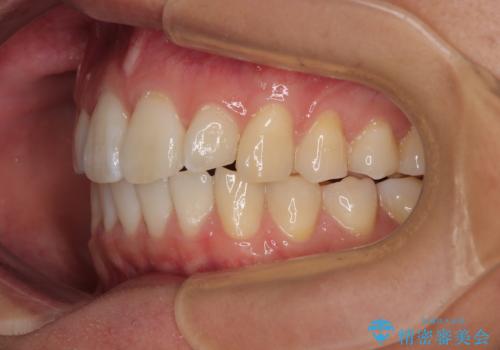

前歯のデコボコをインビザラインで綺麗に改善

- 上下前歯のデコボコとクロスバイトを気にして来院された患者様です。

インビザラインを用い、IPR(歯と歯の間を削る)と歯列全体を拡大させることで、歯並びを整えていくこととしました。

毎日22時間の装着時間を徹底してくださったのですが、左右ともに臼歯が咬合しなくなるという、インビザライン独特の症状が強く長く続いてしまい、終了するまでに長期間を要してしまいました。